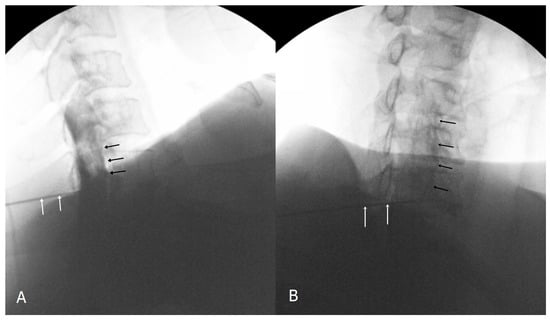

2.2. Injection Technique

2.3. Image and Data Analysis